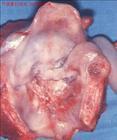

喉癌專題

喉癌的檢查與診斷

喉癌在我國北方比南方發(fā)病率高,城市比農村發(fā)病率高,男性多于女性。發(fā)病年齡多在40—70歲之間。